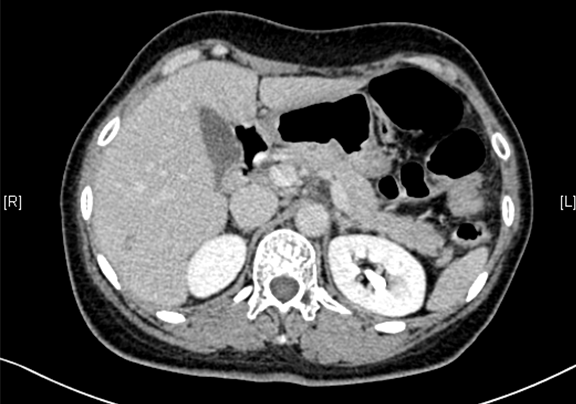

术前CT检查:动脉期

静脉期

平衡期